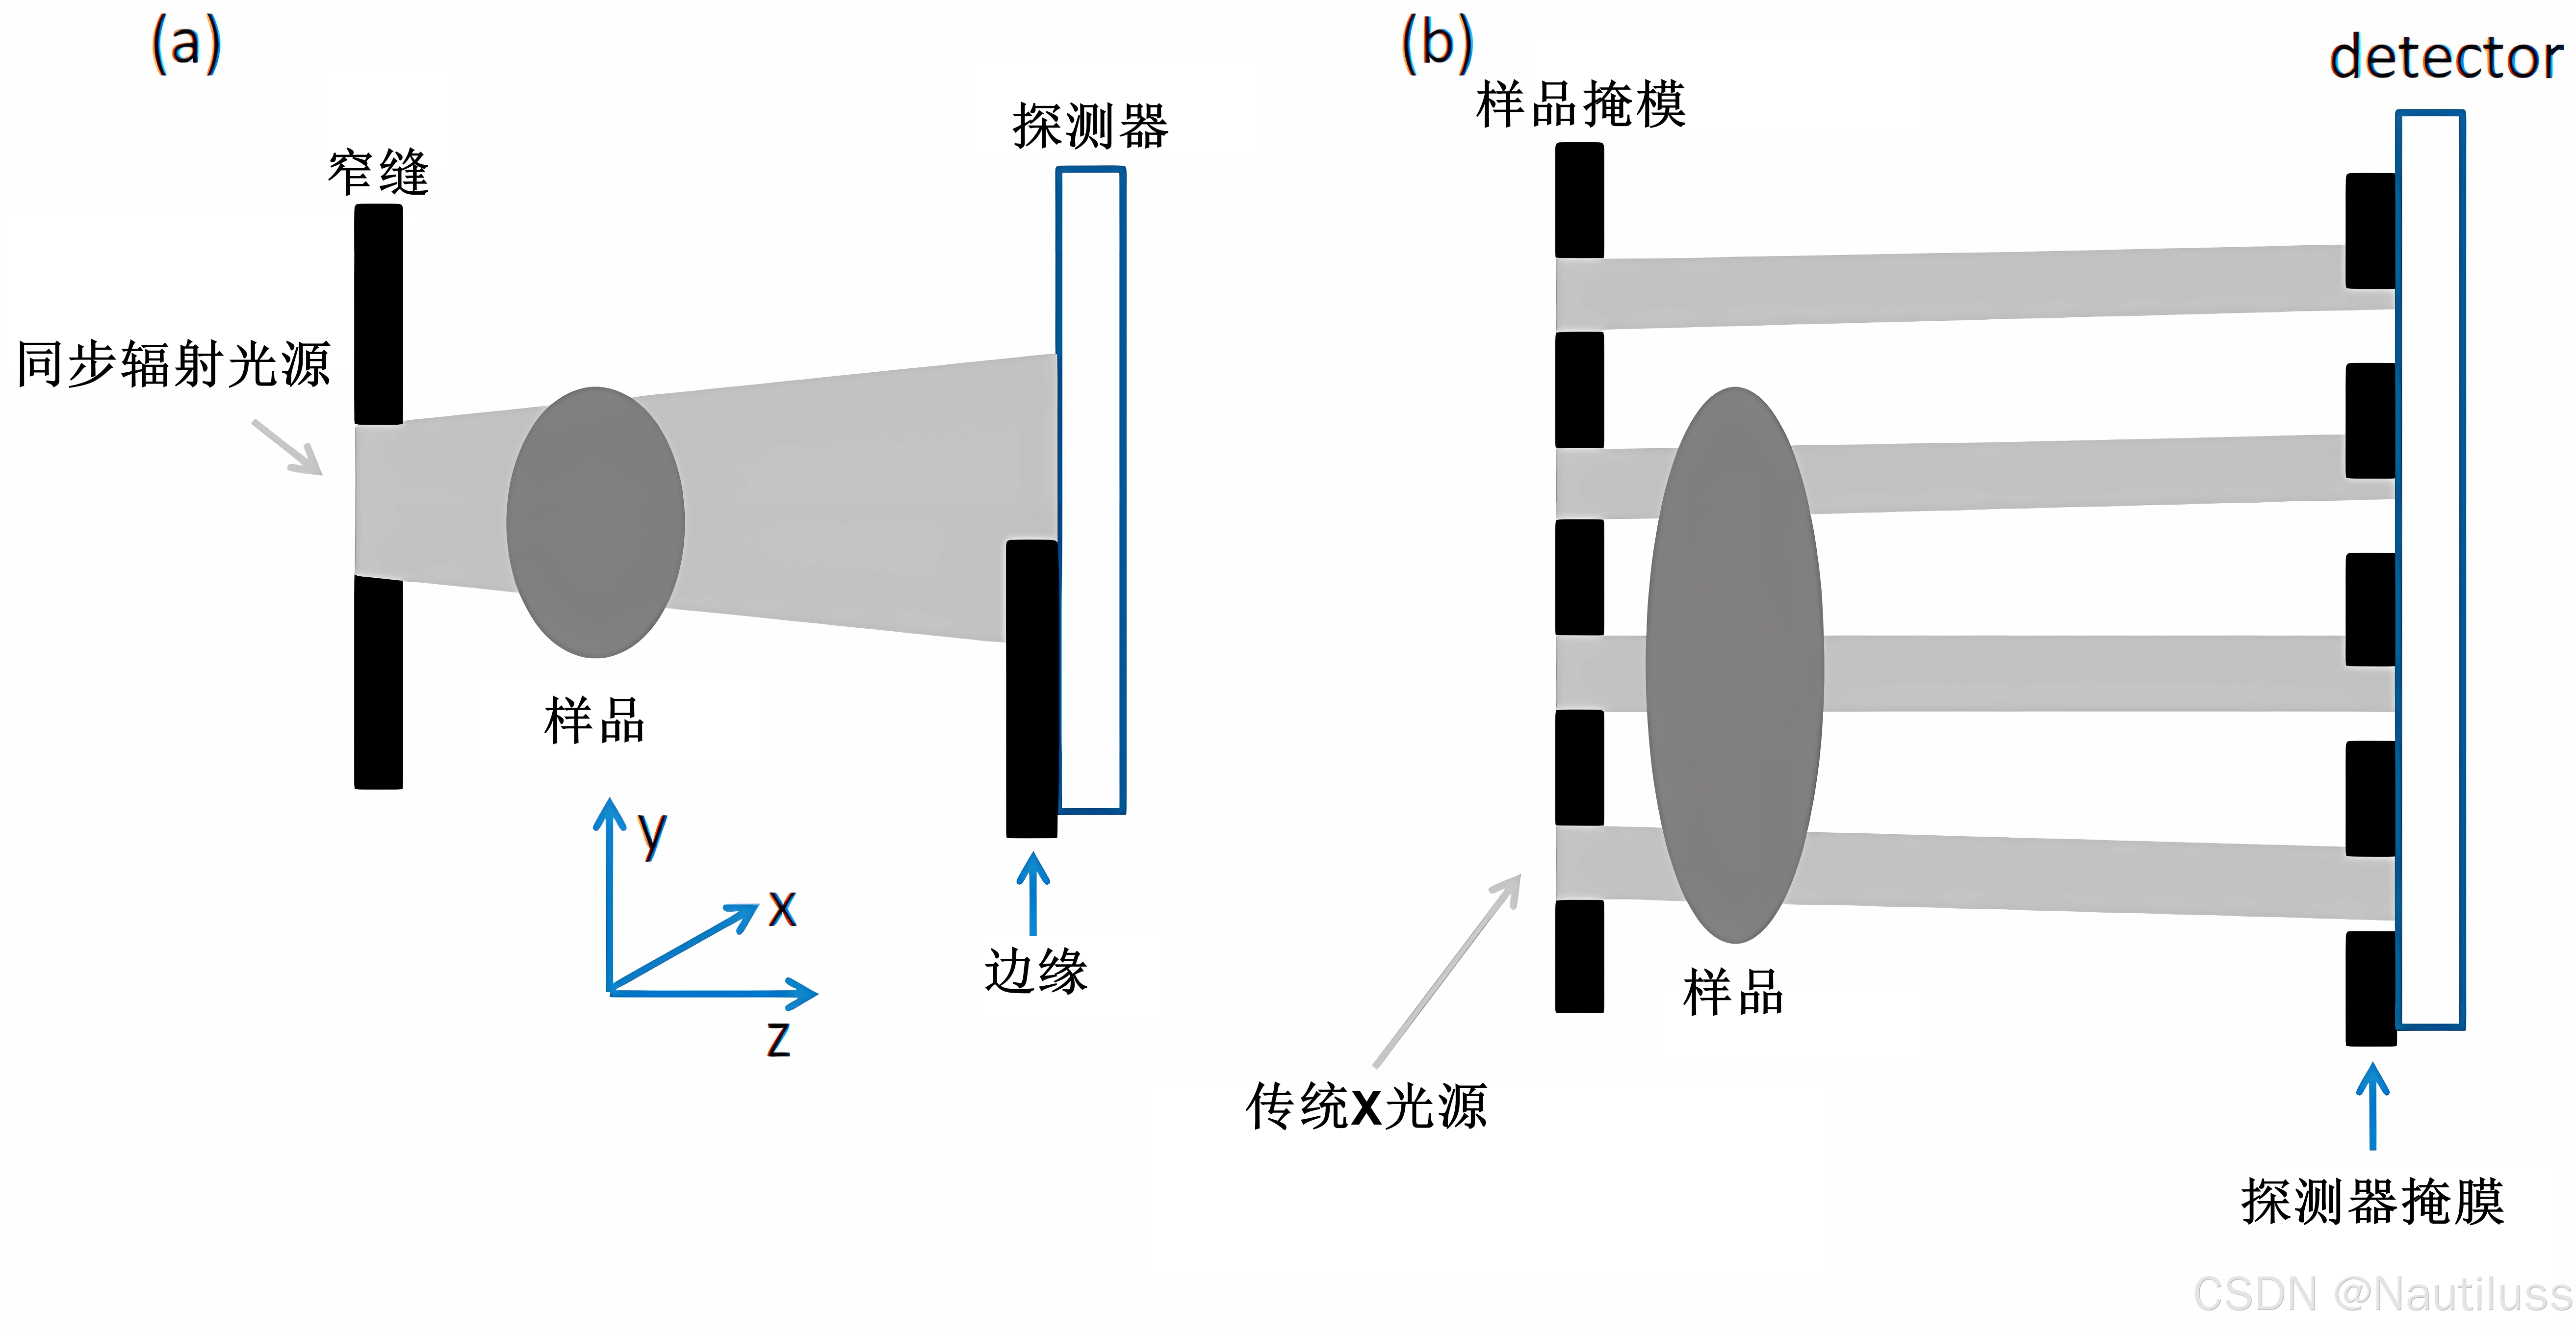

3、边缘照明 (EI)

在边缘照明方法中, X 射线束通过尺寸通常为几微米到几十微米的狭缝准直到一个方向,并与探测器正前方的不透明边缘对齐。部分X射线束被物体折射后被边缘阻挡,其余部分撞击探测器。由于样品的折射,检测器上的 X 射线束位置发生移动,导致检测器中的强度发生变化。如果光束穿透样品,则会获得显示吸收和折射对比度混合的图像。如果采用具有多个孔径的适当掩模,则该方法也可以应用于传统的 X 射线源,但对探测要求很高。

如上图所示,(a)同步加速器辐射的边缘照明(EI)方法。( b ) 使用传统 X 射线源的 EI 方法。边缘照明是一种非相干技术,适用于空间和时间非相干源,无需任何额外的源孔径或准直。它们的纵横比要求不是特别高,掩模价格便宜,易于制造(例如不需要X射线光刻)并且已经可以扩展到大面积。该方法很容易扩展到两个方向的相位灵敏度。